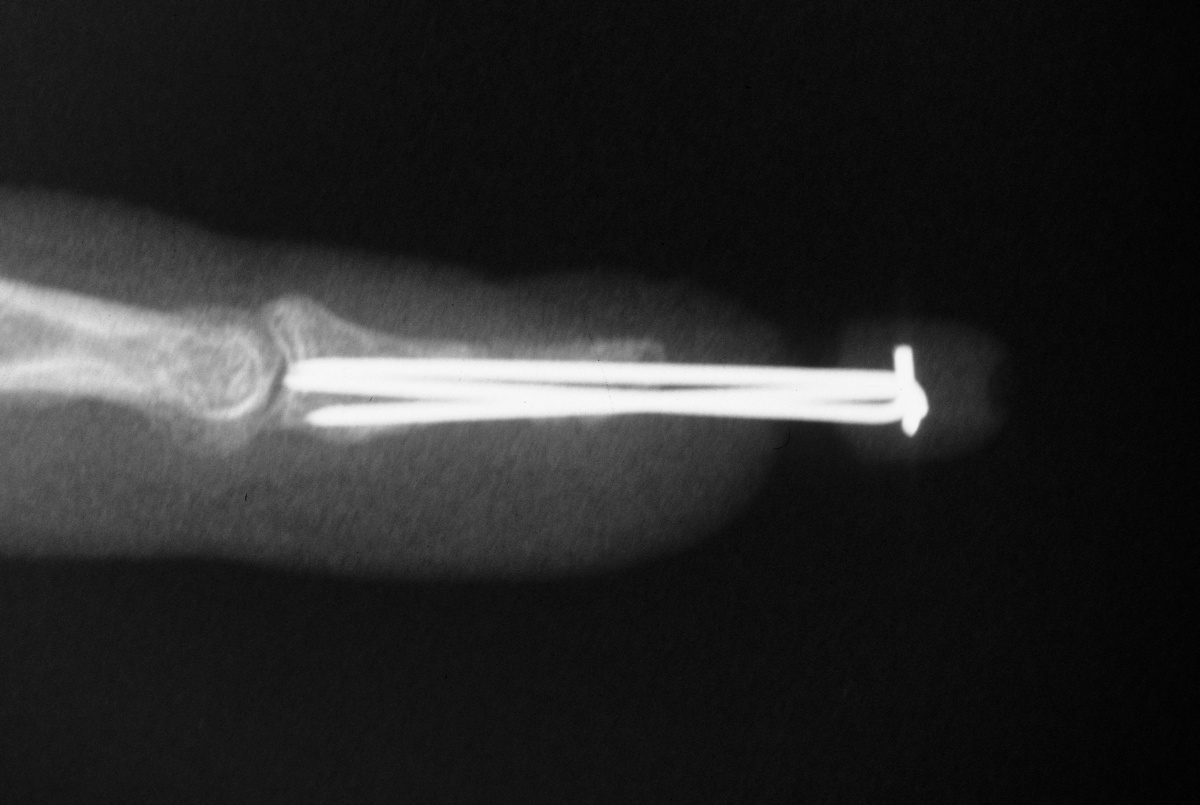

| Case 1. 6 week old grossly unstable distal phalanx fracture. Fracture reduced through a midline palmar approach and stabilized with extraarticular nonparallel Kirschner wires. |

| The K-wires were

bent to form a zone of overlap which was bonded

together with thermoplastic splint material. |

| Pins were removed

at 5 weeks with uneventful fracture healing. |